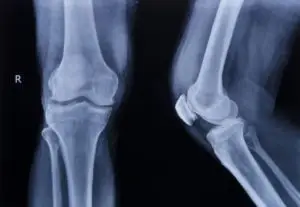

The medical expenses associated with these forms of treatment can produce a serious financial burden, especially when the injury impacts a person’s ability to work and earn a living. The overall effect of a bone or ligament injury varies depending on a person’s age, gender and overall health. Some common bone and ligament injuries include:

- Fractures – compound fractures, displaced fractures, hairline fractures, spiral fractures, crushed or compressed vertebrae, hip fracture, rib fracture, arm or leg fracture, etc.

- Tendon and ligament tears, sprains and strains

- Knee – ACL, MCL & PCL tears, torn meniscus, patella injuries